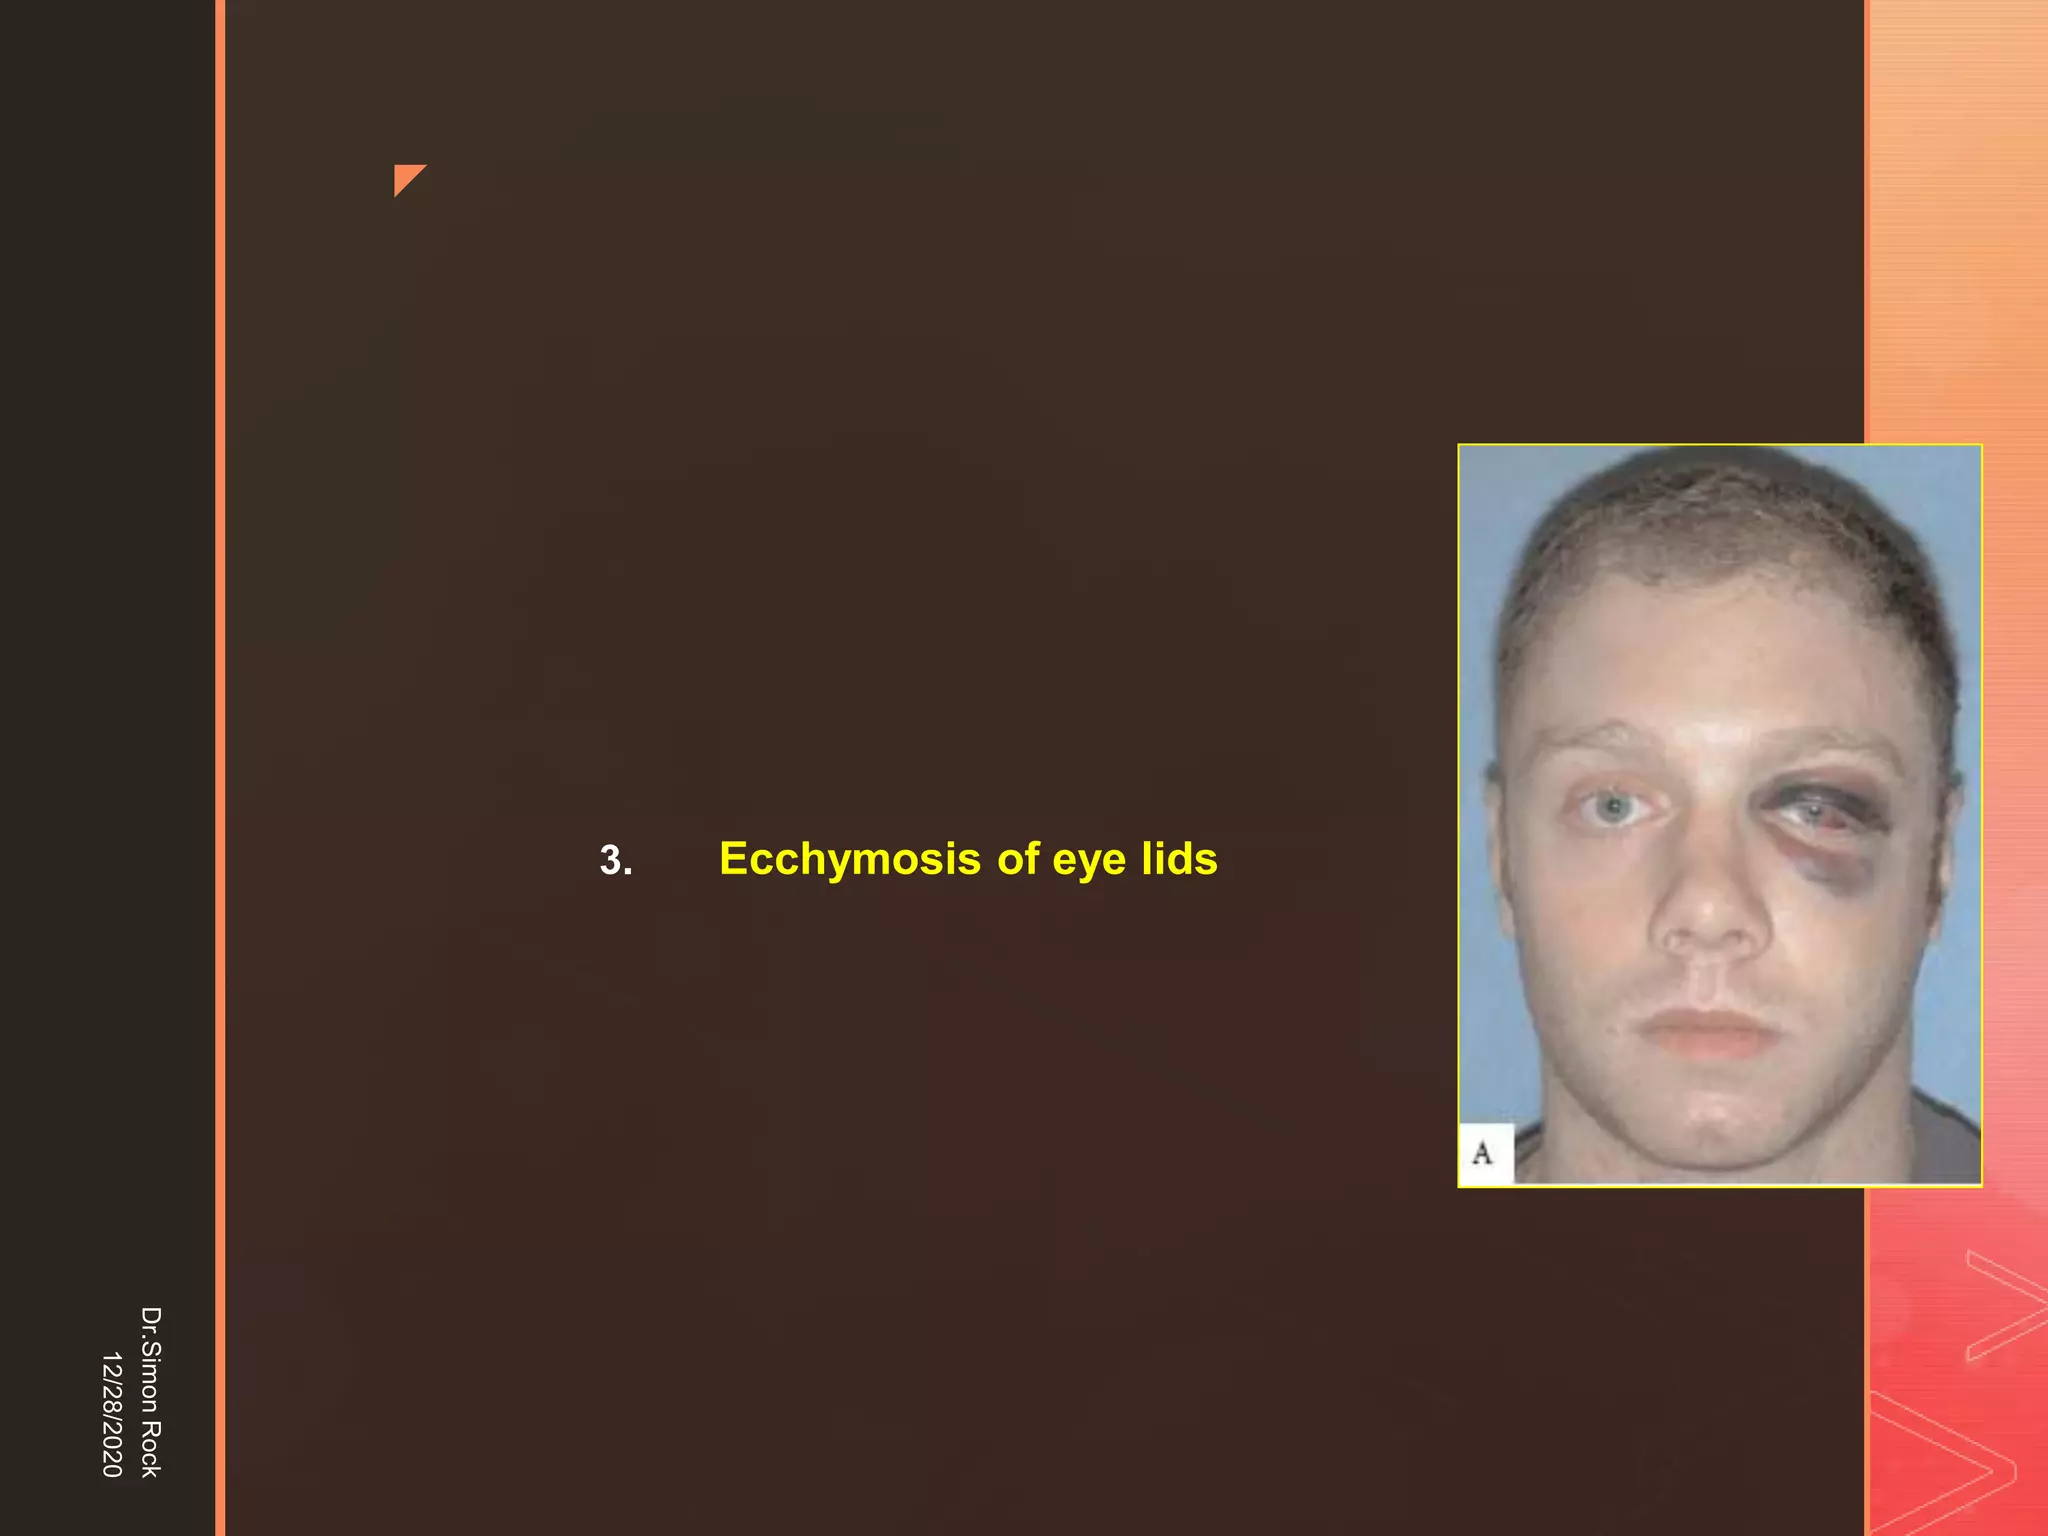

This document discusses the anatomy and fractures of the zygomatic bone. It notes that the zygoma forms the cheekbone and articulates with several other facial bones. Zygomatic fractures most commonly occur in the arch or body due to blunt trauma. Diagnosis involves checking for diplopia, ecchymosis, and other signs of orbital or facial bone involvement. Treatment may involve closed or open reduction based on the severity of displacement. Closed reduction techniques try to elevate the bone back into position without surgery, while open reduction requires surgical exposure and fixation of the fracture site.